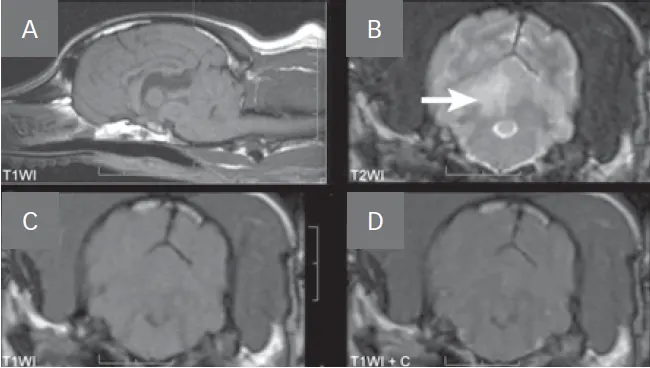

• Diffusion weighted imaging (DWI; Figure 2, see image gallery below) is the sequence of choice for acute ischemic infarction.

• DWI detects lack of normal Brownian motion of molecules, particularly lack of intercellular water movement from cell swelling associated with cytotoxic edema.

• An acute infarction appears as a hyperintense region.